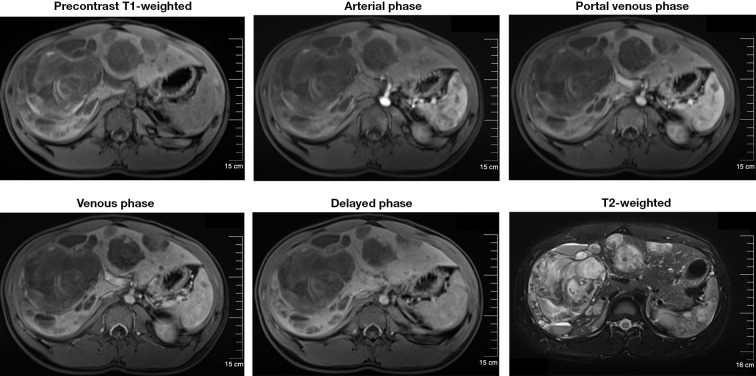

Case description: In the present report, a young male presented with right upper quadrant abdominal pain and hemoperitoneum was eventually diagnosed as hepatic angiosarcoma based on the immunohistochemical staining results of a liver needle biopsy. Contrast-enhanced ultrasound (CEUS) effectively improved the accuracy of the liver needle biopsy in this case. This report describes the epidemiology, presentation, laboratory tests, imaging findings, and pathological features of a rare hepatic angiosarcoma seen in this young male. The patient rapidly developed severe abdominal hemorrhage. Transcatheter hepatic artery embolization, blood transfusions, and symptomatic treatments were administered. The family members abandoned treatment because the patient was in critical condition and could not receive antitumor therapy.

Conclusions: This case emphasizes the significance of pathological findings in the diagnosis of PHA especially in non-high-risk individuals, and the supportive role of CEUS in guiding the liver needle biopsy. Abdominal hemorrhage is one of the serious complications of PHA and transarterial embolization (TAE) should be considered for controlling life-threatening bleeding from ruptured tumor. Further investigation is required to early diagnosis and to improve the prognosis of patients with PHA.